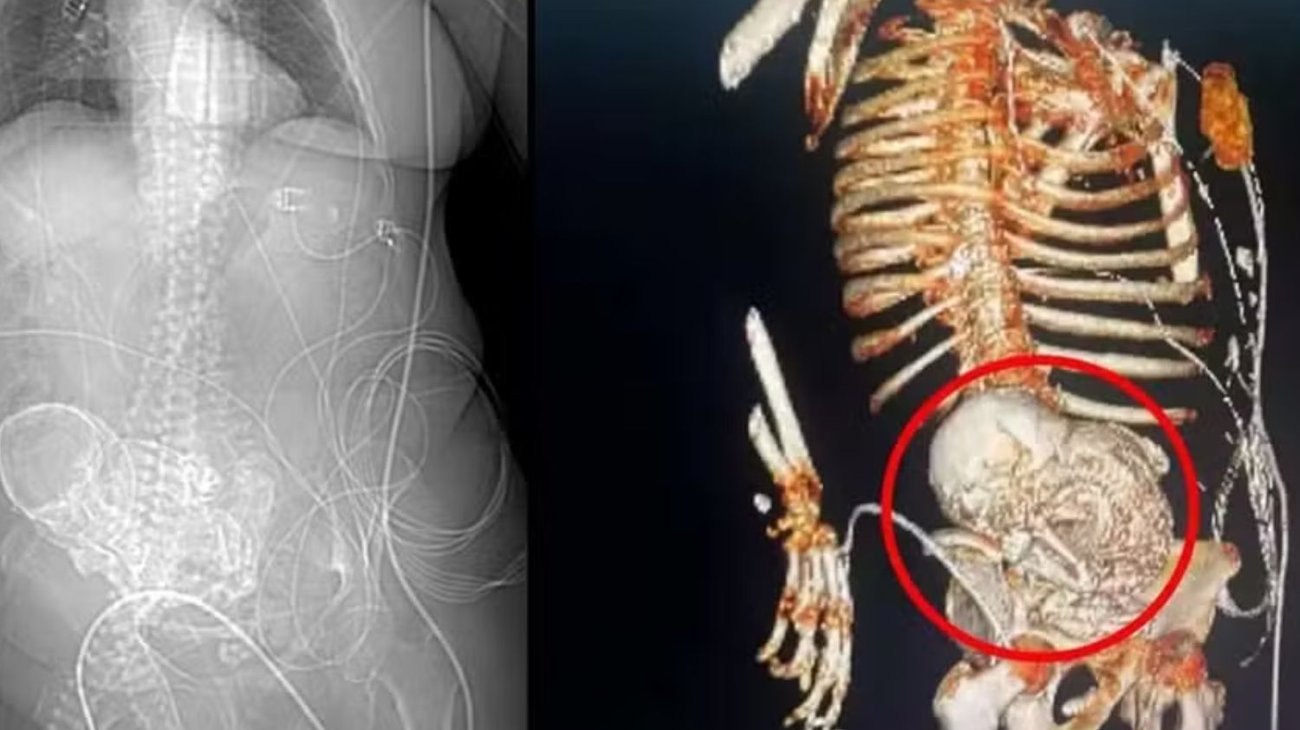

La anciana acudió al Hospital Regional Dr. José de Simone Netto, en la ciudad de Ponta Porã, el pasado 14 de marzo con una infección grave y le realizaron una tomografía, momento en el que el equipo médico descubrió que la mujer tenía un "feto calcificado".

Se trata de una condición rara denominada 'litopedia', que significa "bebé de piedra" y es causada por un óvulo que se fertiliza fuera del útero y deriva en la muerte del feto y su posterior calcificación.